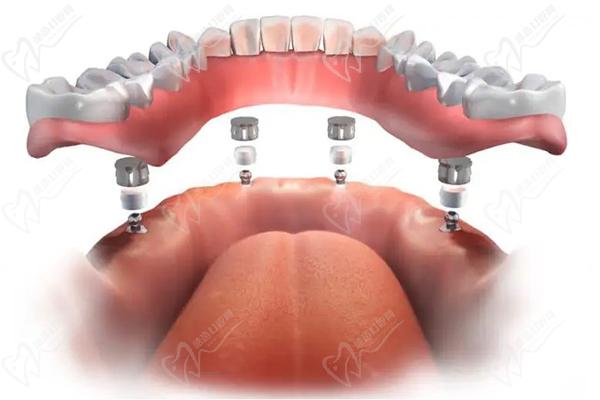

柯威爾種植體在韓國(guó)種植體排名前三位置,是韓國(guó)植體中的高端品牌,臨床反饋數(shù)據(jù)好,做半口、全口種植牙成效更好,愈合也更快。